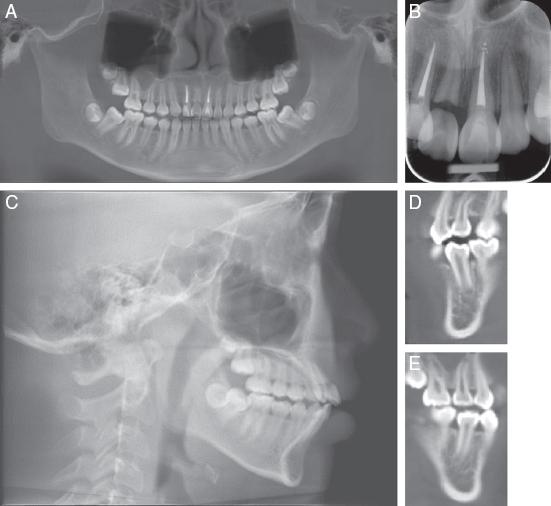

Figure 1.